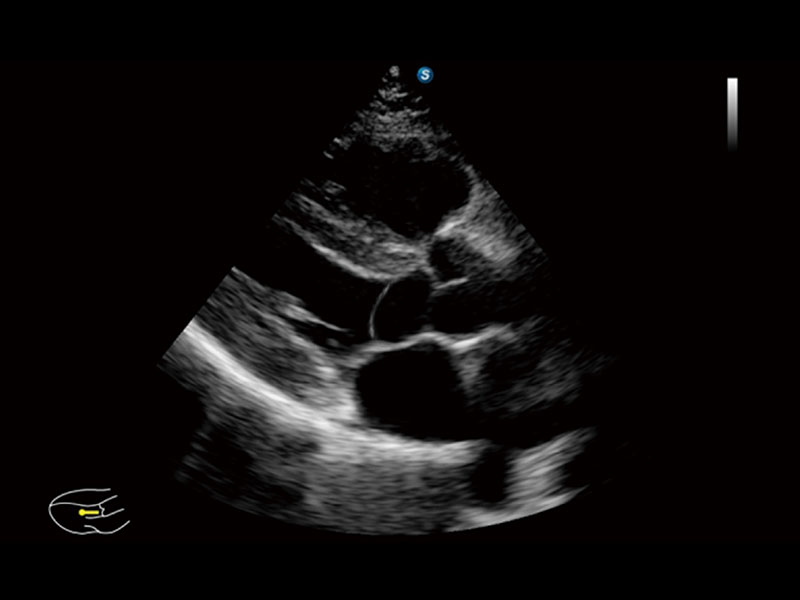

作为开立医疗全新打造的高端床旁笔记本超声,E11不仅具备卓越的图像质量,同时搭载全面高效的自动测量工具,助力医生实现更快速、更精准的床旁诊断。

E11搭载了丰富的自动化测量工具,以及专为POC科室定制的高级功能;同时配备了为急诊医师量身打造的 SonoFast急重症超声流程,以帮助临床医生最大限度的提升工作效率